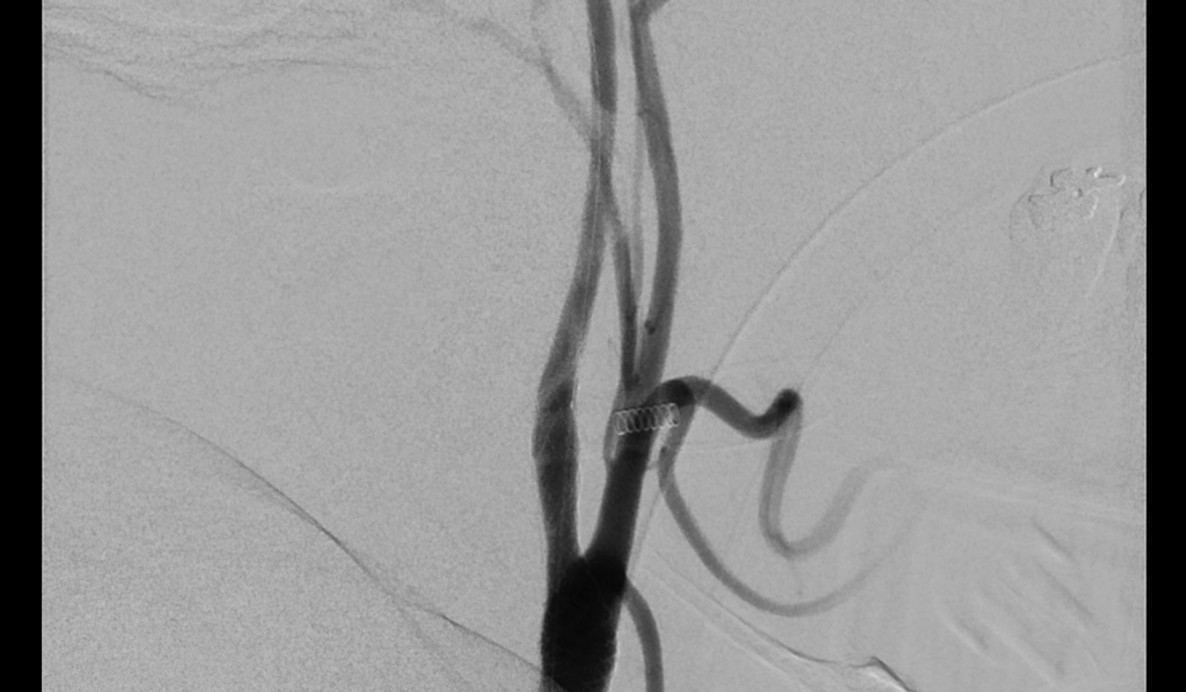

Eingeliefert wird Mathias Zierke vom Rettungsdienst als akuter Notfall in die Medizinische Universität Lausitz – Carl Thiem (MUL – CT), die aufgrund ihrer zertifizierten überregionalen Schlaganfallstation auf genau solche Fälle spezialisiert ist. „Auf der Fahrt bin ich kurz wachgeworden. Ansonsten habe ich ganz schwache Erinnerungen an den Morgen“, sagt Zierke. In der Zentralen Notaufnahme wird der Forster vom Team der Neurologie und Radiologie übernommen. Aufgrund der Symptomatik wird von einem Schlaganfall ausgegangen und eine Computertomografie des Kopfes und der hirnversorgenden Arterien initiiert. Nach Auswertung der Untersuchung bestätigt sich der Verdacht: Verschluss der mittleren Hirnarterie durch einen Thrombus, der sich an der hochgradigen Verengung der Halsschlagader gebildet hat. Mathias Zierke wird nach medikamentöser Behandlung mit einem blutgerinnselauflösenden Medikament umgehend zur weiteren minimalinvasiven Eröffnung des Verschlusses in die Angiografie gebracht.

„In einem minimalinvasiven Eingriff führen wir für gewöhnlich einen Katheter von der Leistenarterie ein und navigieren ihn über einen dünnen Draht bis unmittelbar vor den Thrombus in der verschlossenen Hirnarterie“, erläutert Dr. Stefan Kliesch, Chefarzt Diagnostische & Interventionelle Neuroradiologie an der MUL – CT, „wobei wir bei Herrn Zierke die für den Thrombus ursächliche hochgradige Verengung der zuführenden Halsarterie schnell passieren konnten.“

Der Thrombus in der Hirnarterie kann entfernt und die zugrundeliegende Gefäßverengung am Hals mit einem Stent und einem kleinen Ballon geweitet werden.

„Der gesamte Eingriff dauert dabei nicht einmal eine Stunde und Herr Zierke wird noch auf dem Untersuchungstisch aus der Narkose erweckt“, sagt Dr. Kliesch. Nach dem Eingriff wird er zur Risikoabklärung auf die Stroke Unit des Klinikums verbracht. „Diese hochspezialisierte interventionelle Behandlung des Schlaganfalls kann nur in optimaler Zusammenarbeit von Neurologie, Anästhesie und Neuroradiologie erfolgen“, ergänzt Dr. Antje Herwig, leitende Oberärztin der Klinik für Neurologie.